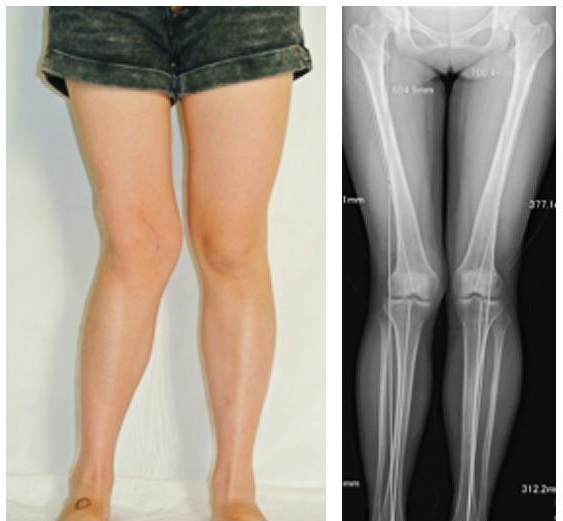

骨性关节炎的发病基础是关节内的软骨退变,当软骨出现了损伤以后,关节内的磨损就会越来越加重。随着病情的加重,会出现软骨下骨的硬化以及骨质增生,也就是骨赘的形成,当病情进一步的进展会导致关节的间隙变得狭窄,患者就会出现明显的关节畸形,如果是内侧关节间隙的狭窄,会导致患者出现o型腿,如果是外侧间隙的关节狭窄会导致患者呈现为x型腿。

前面已经说到骨关节炎会导致骨赘的形成以及关节间隙的狭窄,所以我们依靠膝关节x片子来初步判断骨关节炎的病情,通常我们采用K_L分期判断病情。